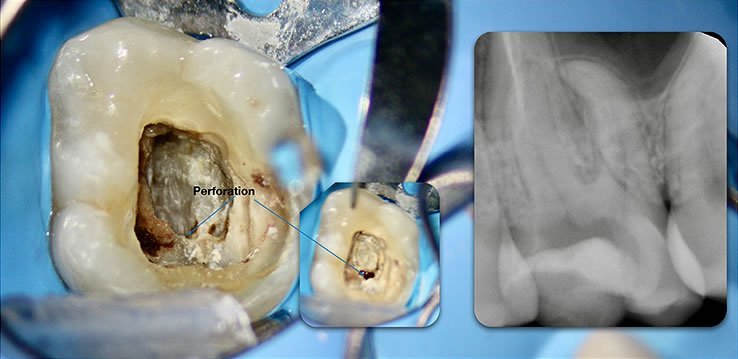

Template for x-rays